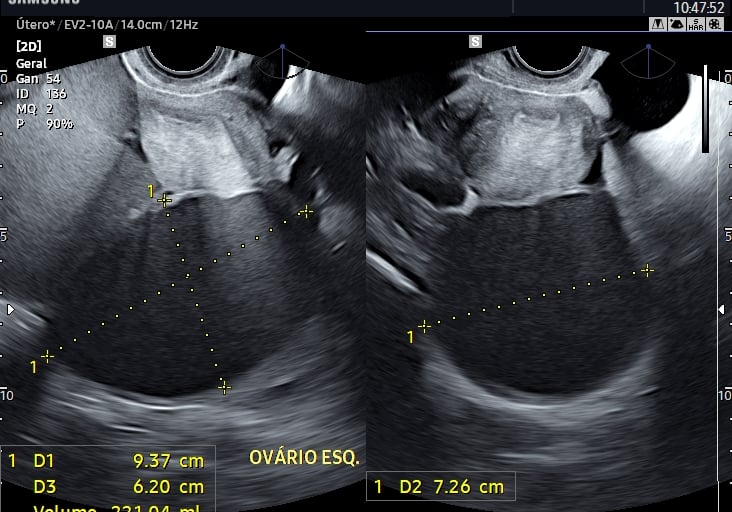

A ultrassonografia pélvica é fundamental para a avaliação do útero, ovários e outras estruturas da pelve feminina. A via transvaginal oferece imagens mais detalhadas e é amplamente utilizada na investigação de patologias ginecológicas.

Avaliação de cistos ovarianos;

A endometriose é uma condição comum que pode causar dor pélvica e infertilidade. O ultrassom especializado, principalmente o transvaginal com preparo intestinal, pode detectar implantes endometrióticos profundos e orientar o tratamento.